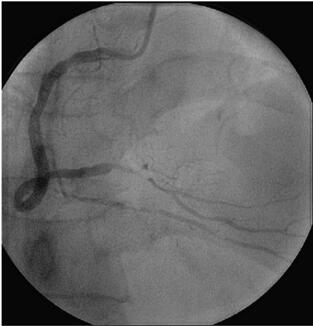

冠状动脉造影(图058‐2、图058‐3)多体位造影显示:冠脉呈右冠优势型,L M开口见90%局限性狭窄;LAD 管壁不光滑,近段见90%局限性狭窄,D1 开口后次全闭塞,中段见85%弥漫性病变,远端血流TI MI 3 级;LCX 管壁不光滑,远端90%局限性狭窄,OM1分叉处Ⅰ型分叉病变,最窄处约80%,远端血流TI MI 3 级;RCA 管壁欠光滑,远段见85%偏心性狭窄,PDA 开口前分叉病变,最窄处约95%,远端血流TI MI 3 级。

图058‐2 冠状动脉造影

图058‐3 冠状动脉造影